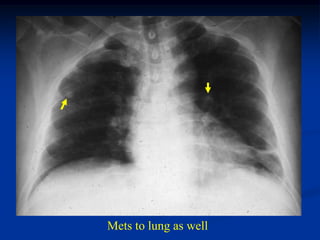

Case #1155              Metastatic Hepatoma

62yr male with metastatic hepatoma prox femur with fracture

Lateral view

Post op ORIF

Mets to lung as well